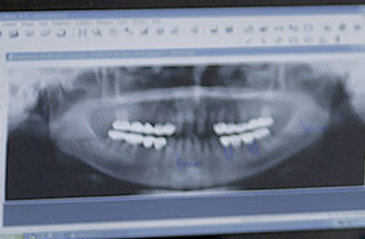

Röntgen

Mit modernster digitaler Röntgentechnik – für ein maximales Ergebnis bei minimaler Strahlenbelastung. Digitales Röntgen ist aus der modernen Problemfeststellung nicht mehr wegzudenken. Die Vorteile gegenüber der herkömmlichen Verfahren sind offensichtlich: Die Strahlenbelastung ist zum Teil bis zu 90% reduziert, Bildergebnisse sind sofort sichtbar, die Bildqualität ist erheblich besser und die digitalen Bilddaten sind für weitere Behandlungsschritte einfach weiterzugeben und zu vervielfältigen.

Digitales OPG Röntgen